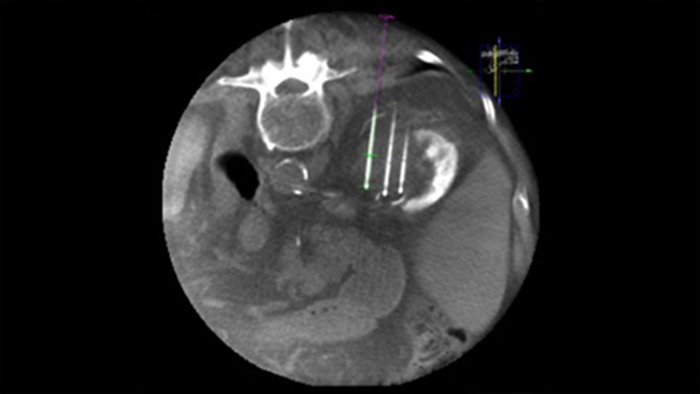

La ablación percutánea (radiofrecuencia, microondas y crioablación) es un tratamiento mínimamente invasivo bien establecido para los tumores de riñón, hígado, pulmón y hueso. Es fundamental definir los límites del tumor y decidir el número óptimo de agujas y la correspondiente trayectoria de estas para poder realizar un tratamiento completo del tumor y no causar daños en el tejido circundante. Navegar con precisión con baja dosis hasta la lesión de interés sin reposicionar la aguja aumenta las posibilidades de éxito y reduce el riesgo de complicaciones de las biopsias o ablaciones. La confirmación del punto final del tratamiento de ablación puede realizarse con imágenes en 3D mientras el paciente sigue en la mesa.

SmartCT Soft Tissue ofrece una técnica de adquisición mediante TC de haz cónico (CBCT) aumentada con guía paso a paso, visualización 3D avanzada y herramientas de medición; todo accesible en el módulo de pantalla táctil desde la mesa.